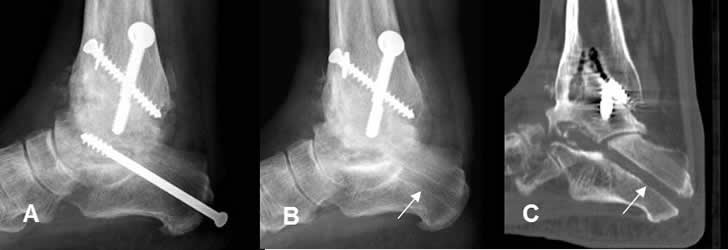

Fig 113 A. Infección del material.

A: Rx AP. Fractura desplazada del maleolo interno.

B: Rx AP. Reducción y fijación con tornillos.

C: Rx AP. Edema de tejidos blandos en el tobillo y osteolisis del calcáneo y ambos maleolos por osteomielitis, lo cual obliga a retirar el material y coloca tutor externo.

D: Rx AP. Como secuela queda artropatía neuropática hipertrófica y artrosis de la articulación.